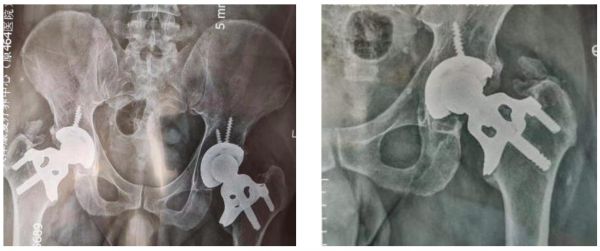

据了解,公司目前的人工关节产品已经完成了上亿次的疲劳实验,理论使用寿命达到60年。同时,产品可靠性得到了初步的验证:董荣华主任亲属11年前因双侧股骨头坏死,完成了缓冲式无柄髋关节置换术,目前复查良好,无任何临床症状。

无柄髋关节置换术11年